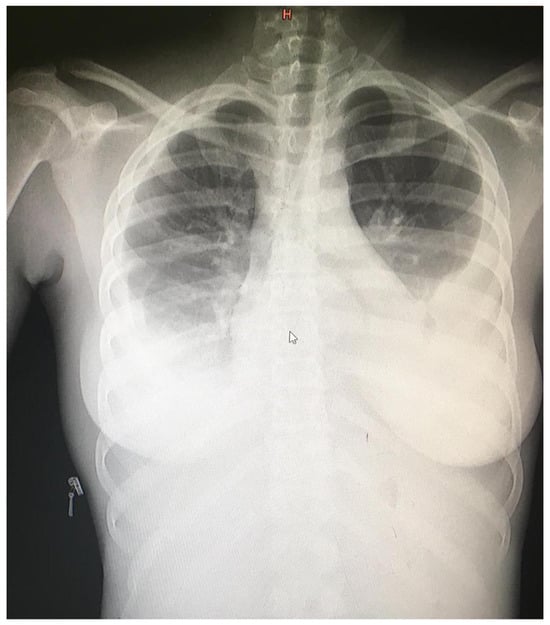

| Day 39 | Clinic visit for paclitaxel cycle 3 with repeat laboratory examinations and ultrasound. Reported adherence to ART regimen. |

| Day 116 | Post treatment follow up visit in clinic with repeat laboratory examinations and ultrasound. Patient felt well and was back in school. |